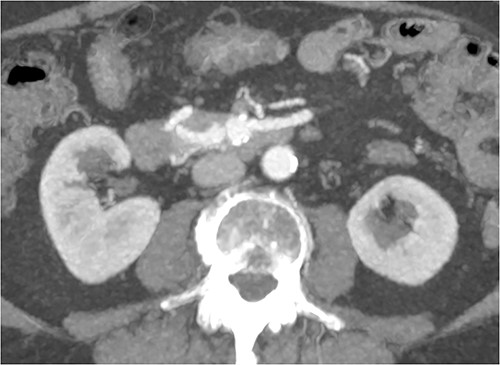

CT of abdomen and pelvis was performed, which revealed a 13 mm indeterminate lesion arising between the pancreatic uncinate process and the duodenum with coarse peripheral calcification, suspicious of primary pancreatic neoplasm or primary small bowel cancer (Figs 2–4).

Initial CT: sagittal view of the indeterminate pancreatic/duodenal lesion.